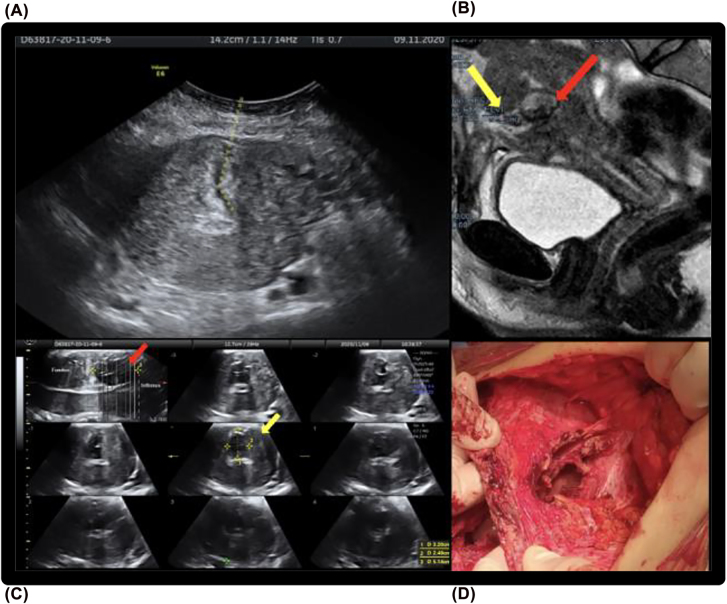

Objectives: The occurrence of a uterocutaneous fistula (UCF) as an uncommon and severe complication of caesarean section (CS). The aim of this study was to describe two cases of UCFs after CS and to discuss about symptoms, diagnosis and treatment.

Case presentation: Both women few days after CS had surgical site infection, fever and elevation of lab inflammation markers. bacterial culture of the wound drainage was positive for Escherichia Coli and Enterococcus Faecalis.

Conclusions: Fistula between uterine and skin is a rare condition but should be considered with signs of inflammation after cesarean section; 2D/3D ultrasound evaluation appears to be useful for diagnosis of UCFs when combined with CT fistulography and MRI in order to obtain early diagnosis and, consequently, a conservative surgery.